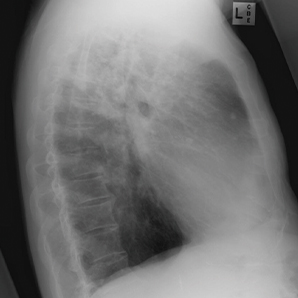

The high-performance imaging chain outputs reliable images as always. Subtle image details elevate diagnosis confidence to meet a broad range of clinical needs.